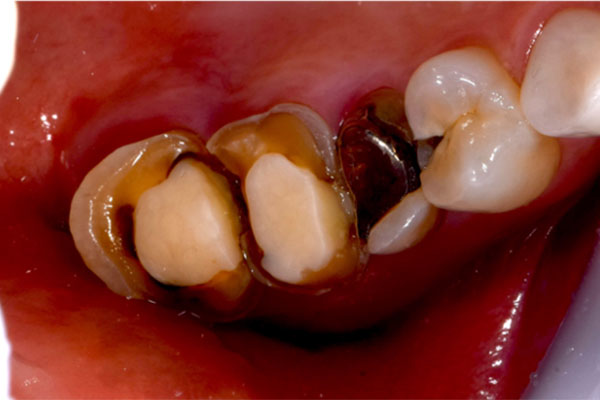

【担当医師所見】

左下奥歯は親知らずが原因でクラウン(かぶせ物)の下まで虫歯になっています。 またその手前の歯は根中央部に大きな透過像(黒い像)が見られます。クラウン除去後、マイクロスコープ下で確認したところ中央部は亀裂が入り保存不可能な状態になっており抜歯となりました。

①親知らず手前の歯はクラウン(白い不透過像)直下に大きな透過像(黒い部分)が見られこのような場合は抜歯になる確率が高いです。

②歯根分岐部(中央部)に及ぶ歯周炎ー根尖性歯周炎の原因はクラウン除去後にマイクロスコープ下にて破折線を確認したため抜歯となりました。

治療前、左上大臼歯部は咬合面(咬む面)も無くカリエス(虫歯)も大きいものでした。